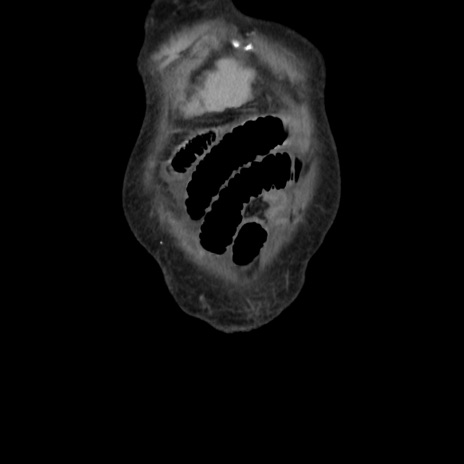

横断像